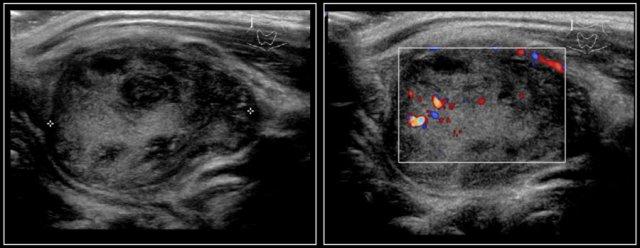

Hashimoto’s thyroiditis: An enlarged thyroid gland with a diffuse inhomogeneous structure and hyperemia is seen in a ten-year-old girl

Các dạng viêm tuyến giáp phổ biến nhất là viêm tuyến giáp Hashimoto và bệnh Graves.

Cả viêm tuyến giáp Hashimoto và bệnh Graves đều có thể biểu hiện là tuyến giáp to và tăng sinh mạch máu.

Trên siêu âm, tuyến giáp to lan tỏa và không đồng nhất.

Trên siêu âm Doppler màu, lưu lượng máu thường bình thường nhưng có thể tăng như trong bệnh Graves.

Trong bệnh Graves, tuyến giáp cũng to ra và cho thấy sự tăng tưới máu.

Trên siêu âm Doppler màu, hình ảnh này được mô tả như một địa ngục lửa với màu đỏ và xanh.

Đây là hình ảnh của một bé gái 16 tuổi mắc cường giáp.

Tuyến giáp to lan tỏa với tình trạng sung huyết.

Chẩn đoán cuối cùng là bệnh Graves.